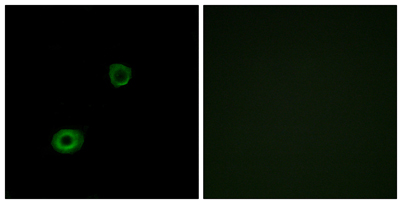

| Product name: | MRGX4 rabbit pAb |

| Dilutions: | WB 1:500-2000;IHC-p 1:50-300 |

| Cellular localization: | Cell membrane; Multi-pass membrane protein. |